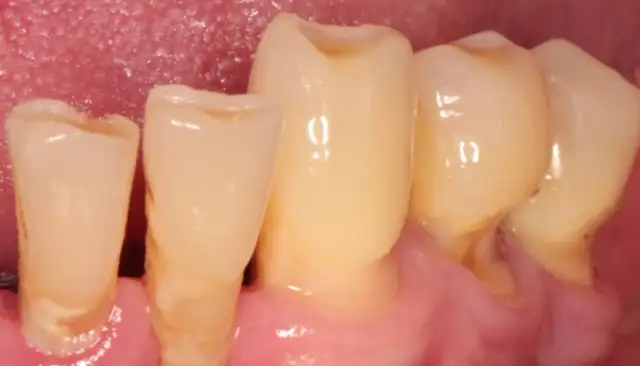

Odsłonięte szyjki zębowe - plomba czy przeszczep? Poznaj opcje

Odsłonięte szyjki zębowe - dowiedz się, kiedy wystarczy wypełnienie, a kiedy potrzebny jest periodontolog. Poznaj przyczyny i skuteczne leczenie.